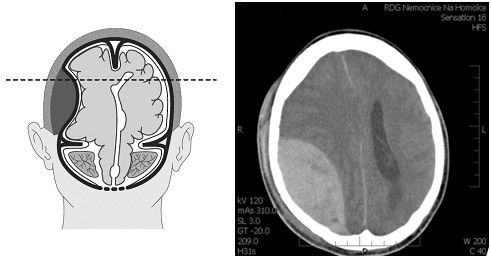

The various common brain herniation types are outlined. Transtentorial herniation (uncal in the diagram) can occur in the opposite direction depending on mass lesion location, and trans-calvarial herniations are not depicted. - Brain contusion

CT-scan of a frontal intracerebral hemorrhage on the right (left image side) as a contre coup. There is dens suture material visible left occipital in the skin.